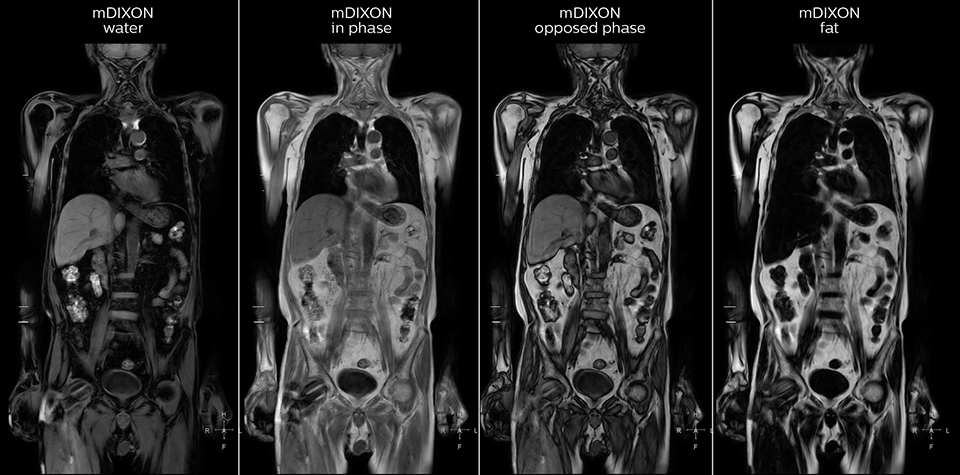

“mDIXON FFE allows us to quickly get information we need to assess the presence of fat. That gives us more information when we need to diagnose bone lesions, and when we are asked to judge fat-containing lesions such as hepatocellular or renal carcinoma,” Dr. Nobusawa says. “The mDIXON fat images can help us to differentiate fatty bone marrow from bone lesions. This is especially useful in elderly people, who tend to have fattier bone marrow. The water images provide a high signal-to-noise ratio in the intestinal canal, which is valuable for visualizing lesions in the colon,” he says.

Kawasaki Sawai Hospital’s whole body protocol also includes an mDIXON FFE sequence. Because mDIXON provides images for four contrast types – water only, fat only, in-phase and out-of-phase – from a single acquisition, it is useful in many ways.

“In-phase and out-phase sagittal T1-weighted FFE images help us to visualize and further characterize bone lesions such as metastasis and bone-marrow hyperplasia that have high signal on DWI. These images are also used throughout radiotherapy, to monitor changes in the fatty bone marrow.”